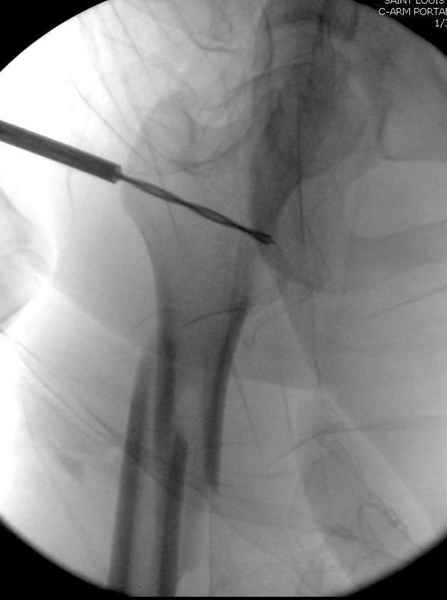

Как раз недавно у меня был примерный случай: больному 36 лет, поступил ночью, травма в результате мотоциклетной аварии, кроме чрезвертельного и спирального перелома левого бедра имеется переломы костей предплечья с этой же стороны. Скелетное вытяжение, а на следующий день больной про оперирован на ортопедическом столе с дистракцией. Чтобы не расколоть чрезвертельный перелом провели временную спицу ближе к переднему кортексу, из малого разреза костодержатель для репозиции, а фиксацию провели антиградным штифтом. Этапы операции на снимках.

Больной долго оставался нестабильным, только на 14 день удалось заменить на антеградный интромедуллярный штифт TFN (trochanteric femoral nail) SmithNephew. После неудачной попытки закрытой репозиции, несмотря на использование "joystick", проксимальный стержень от

наружного фиксатора, (перелом начал срастаться) репозицию провели из малого доступа, затем остальные этапы операции.